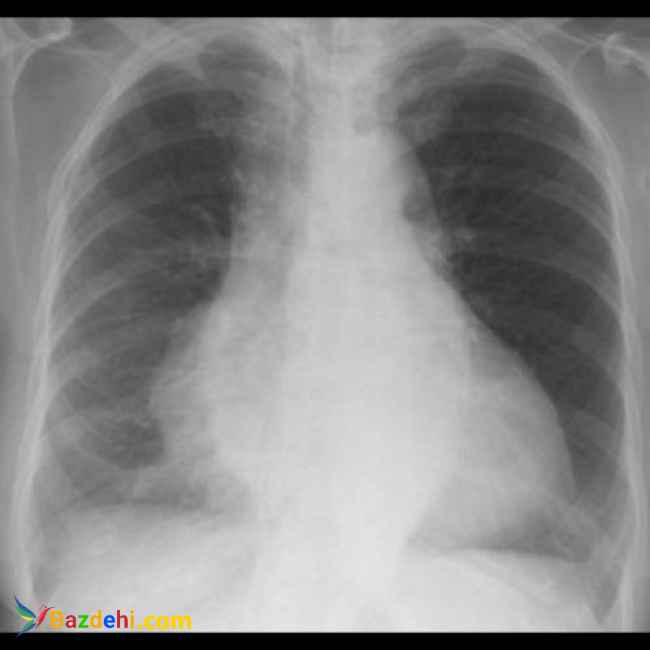

خدمات پزشکی در منزل امید ارایه ی خدمات رادیولوژی و سونوگرافی در منزل به صورت شبانه روزی و بدون تعطیلی در کلیه ی نقاط کشور . تیم تصویر برداری گروه پزشکی امید متشکل از بهترین پزشکان و کارشناسان فارغ التحصیل از دانشگاه های برتر کشور هستند. امروزه با توجه به ترافیک سرسام اور به ویژه در کلانشهرها و همچنین شیوع ویروس کرونا و همچنین هزینه های بالای امبولانس هم از نظر اقتصادی و هم از نظر صرفه جویی در زمان و از همه مهمتر برای پیشگیری از ابتلای به بیماری کرونا، استفاده و بهرمند شدن از خدمات پزشکی و تصویر برداری پرتابل در منزل بیش از پیش همه گیر شده است. و تیم پزشکی امید مفتخر است که با ۱۴سال سابقه در ارایه ی خدمات رادیولوژی پرتابل در منزل و بکارگیری متخصصین بنام کشور و استفاده از بروزترین تجهیزات قابل حمل، در این ایام که پاندمی کرونا نفس سلامتی را تهدید میکند، در کنار هم میهنان عزیز بتواند گرهی از کار خانواده هایی که بیمار در منزل دارند را باز کند. تلفن همراه 1 :09399545088 تلفن همراه 2 :09105545790 تلفن ثابت :02191016923 نام و نام خانوادگی رادیولوژی و سونوگرافی در منزل نام واحد تجاری امید استان تهران امکانات مشاوره رایگان, طرف قرارداد بیمه آدرس سایت: http://Www.omidradiology.ir اینستاگرام: http://Www.instagram.com/radiology_omid آدرس پونک. سردار جنگل جنوبی. میدان استاندارد. پلاک 19 واحد 13 اسکن ریه چیست اسکن ریه در تهران اسکن ریه در غرب تهران اسکن ریه در منزل اسکن ریه در منزل اسکن ریه در منزل پونک اسکن ریه در منزل تهران اسکن ریه در منزل قیمت اسکن ریه شبانه روزی تهران انواع خدمات پزشکی انواع مراکز درمانی تزریقات در منزل تزریقات در منزل پونک تزریقات در منزل غرب تهران تعرفه خدمات پزشکی در منزل تعرفه ویزیت پزشک در منزل تهران تعرفه ویزیت در منزل 1400 تعریف خدمات بهداشتی خدمات ارتوپدی خدمات پرستاری در منزل شرق تهران خدمات پرستاری شرق تهران خدمات پزشکی امید خدمات پزشکی آنلاین خدمات پزشکی چیست خدمات پزشکی در منزل خدمات پزشکی در منزل امید خدمات پزشکی در منزل پونک خدمات پزشکی در منزل تهران خدمات پزشکی در منزل شبانه روزی خدمات پزشکی در منزل غرب تهران خرید دستگاه رادیولوژی پرتابل دکتر ارتوپد دکتر ارتوپد در منزل دکتر کرونا در منزل پونک رادیوگرافی پرتابل چیست رادیوگرافی پرتابل دندانپزشکی رادیولوژی پرتابل در منزل تهران رادیولوژی در منزل رادیولوژی در منزل پونک رادیولوژی در منزل تهران رادیولوژی در منزل شرق تهران